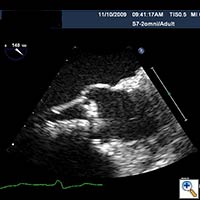

- The Sapien valve is then delivered through the introducer sheath and positioned across the aortic annulus with 50% of the valve above the annulus and 50% below the annulus. Both TEE and aortic root injection are used to confirm the position of the valve and its spatial orientation. Ideally, the valve should be in line with the long axis of the ascending aorta and perpendicular to the aortic annulus (Figure 3, 4, 5).

Figure 3. Direct echocardiographic visualization of the left ventricular outflow tract during valve insertion.